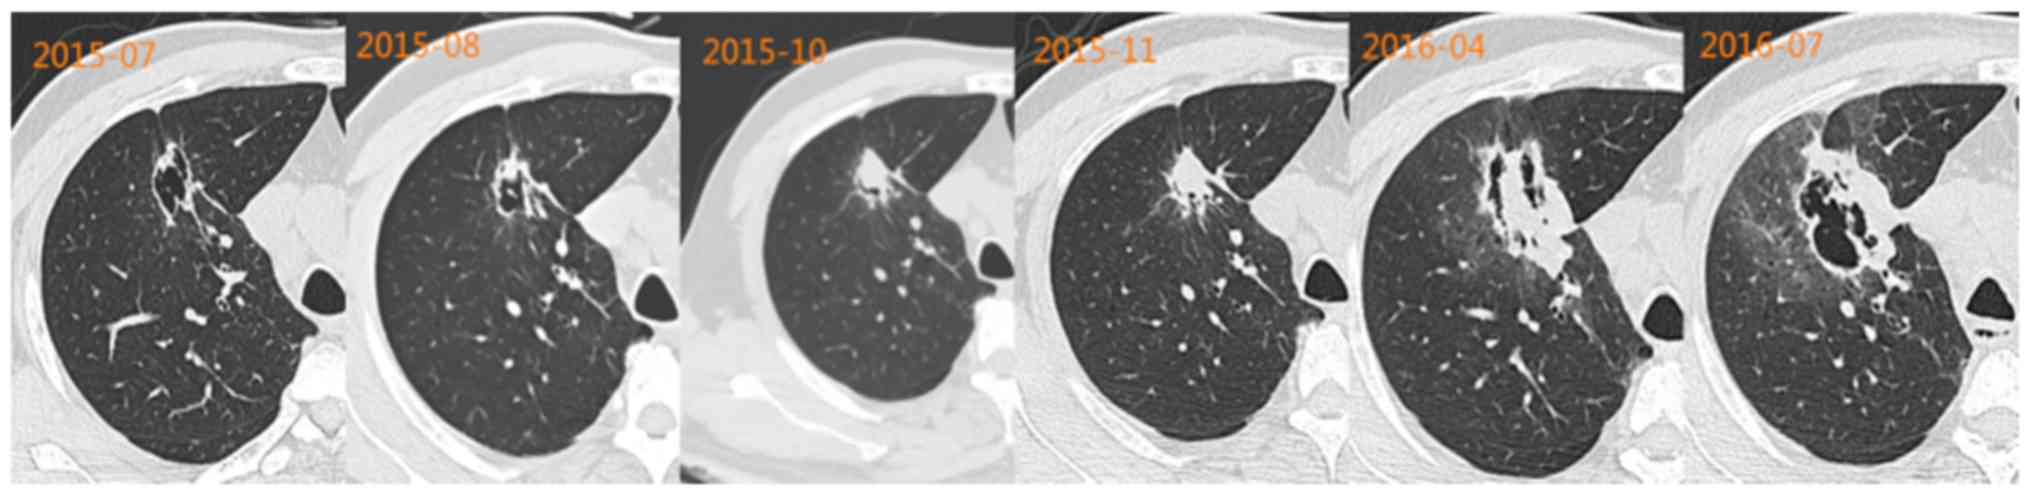

One 60-year-old patient who had interstitial lung disease presented with a small cystic lesion on CT images in January 2016. A chest CT performed after a month revealed that the cystic lesion had become larger, and its wall had become slightly irregularly thickened, compared with the previous CT findings. Close clinical follow-up on a monthly basis was recommended for the patient. Over the following two months, the cystic lesion grew larger than previously and seemed to be uniform in size, but its wall became irregularly thickened with certain malignant observations, including irregular margin, small spicules, signs of pleural indentation, ground-glass opacity and clear nodules. This cystic lesion was suspected to be a malignant lesion. Finally, imaging examinations revealed that the cystic lesion was getting smaller and the wall was getting thicker (Fig. 4).

A cystic lesion was identified in the right upper lung of a 51-year-old patient, who had a long history of smoking and occasional bloody sputum, when he was admitted to hospital for fracture. PET/CT revealed a highly metabolic lesion with multiple highly metabolic lymph nodes in the right hilum. Pathology revealed a poorly differentiated adenocarcinoma with multiple lymph node metastases, and the patient received Iressa (250 mg once a day). Patients were followed up since 2015. Imaging examinations revealed an increasingly smaller cyst and increasing parenchyma. In the final imaging scans, formation of a new cavity was noted (Fig. 5).